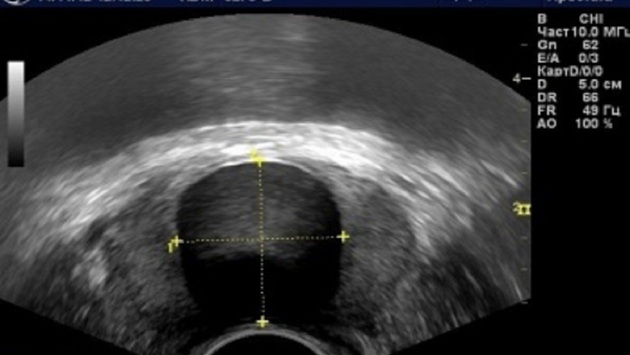

В Новосибирской области стали чаще выявлять рак простаты. В результате на сегодняшний день в структуре онкологических заболеваний данная патология занимает третье место.

При этом, отметили в Новосибирском областном онкодиспансере, у 73,5% больных болезнь выявлена на ранней стали. Всего на сегодняшний день рак простаты диагностирован у 1405 жителей региона.